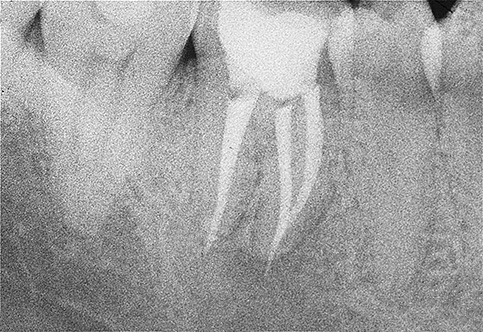

Dopo avere deterso e sagomato i canali radicolari si passa all’otturazione degli stessi con guttaperca calda e quindi al sigillo coronale (nuova otturazione o corona), fase finale che impedisce la re-infezione batterica dei canali stessi.

E’ molto importante monitorare nel tempo il ritrattamento, eseguendo radiografie di controllo a distanza che documenteranno le modificazioni morfologiche della lesione periapicale e consentiranno al clinico di pronunciarsi in merito alla guarigione e alla prognosi del singolo caso.